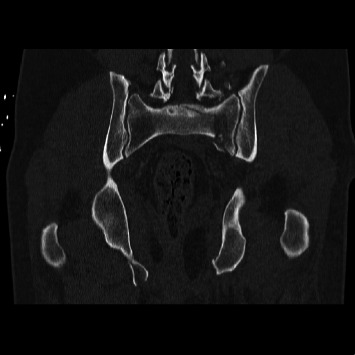

导读:脊柱骨盆分离是一种毁灭性的损伤,由于其复杂性和低发病率,仍然难以管理。腰椎骨盆固定是一种传统的治疗选择,采用开放入路。然而,在严重的多发创伤患者中,开放式固定与大量失血和感染风险相关。技术的进步使得这种手术可以经皮进行。因此,我们评估了接受开放式腰骨盆固定和接受经皮腰骨盆固定的患者之间的结果。方法:回顾性分析2012年至2024年接受开放或经皮腰骨盆固定治疗脊柱骨盆分离的患者。采用AOSpine分类系统对所有骨折进行分类。分析患者人口统计学、临床和手术结果。结果:48例脊柱骨盆分离患者纳入最终分析,其中21例接受开放式腰骨盆固定,27例接受经皮腰骨盆固定。两组患者术前特征和人口统计学相似。经皮组出血量明显减少(82 mL vs. 679 mL;P < 0.01),手术时间较短(168∶284 min;P < 0.01),手术部位感染较少(0比4;p=0.03),降低了手术室成本(35,097美元vs. 23,743美元;P =0.01),但盆腔前环损伤率较高(63% vs. 19%;p = 0.003)。两组患者的住院时间(p=0.63)和随访时间(p=0.64)均无统计学差异。结论:我们的研究结果表明,经皮腰盆腔内固定术是一种具有吸引力的微创且时间短的治疗脊柱盆腔分离的方法,而且不会增加发病率。

Introduction: Spinopelvic dissociation is a devastating injury that remains difficult to manage due to its complexity and low incidence. Lumbopelvic fixation is a treatment option traditionally performed with an open approach. However, open fixation is associated with substantial blood loss and infection risk in critical polytrauma patients. Technological advancements have enabled this procedure to be performed percutaneously. Thus, we evaluate outcomes between patients receiving open lumbopelvic fixation and those receiving percutaneous lumbopelvic fixation. Methods: A retrospective review was conducted of patients undergoing either open or percutaneous lumbopelvic fixation for spinopelvic dissociation from 2012 to 2024. The AOSpine classification system was used to classify all fractures. Patient demographic, clinical, and operative outcomes were analyzed. Results: 48 patients with spinopelvic dissociation were included in the final analysis, with 21 receiving open lumbopelvic fixation and 27 receiving percutaneous lumbopelvic fixation. Preoperative characteristics and demographics were similar between the two groups. The percutaneous group demonstrated significantly reduced blood loss (82 vs. 679 mL; p < 0.01), shorter operative time (168 vs. 284 min; p < 0.01), fewer surgical site infections (0 vs. 4; p=0.03), and reduced OR cost ($35,097 vs. $23,743; p=0.01) but had a higher rate of anterior pelvic ring injuries (63% vs. 19%; p=0.003). There was no significant difference in length of stay (p=0.63) or length of follow-up (p=0.64). Conclusion: Our findings suggest that percutaneous lumbopelvic fixation offers an attractive less invasive and shorter procedure to treat spinopelvic dissociation without added morbidity.